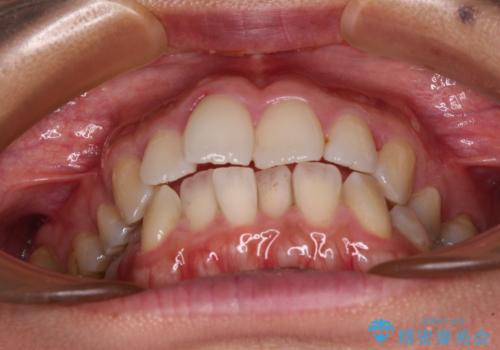

前歯のデコボコを改善 インビザラインの矯正治療

- 前歯のデコボコを治したいとのことで来院された患者様です。

上下顎ともに歯列全体の後方移動とIPR(歯と歯の間を削る)によってデコボコが解消するように設計し、インビザラインにより治療を行うこととしました。